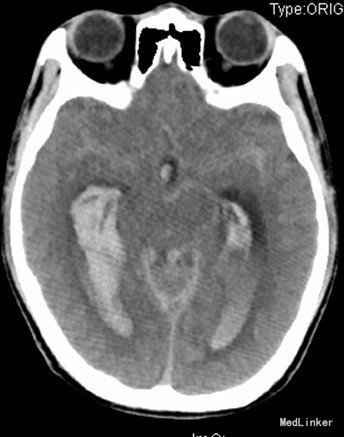

查体:昏迷,双瞳大形圆约3mm,四肢及肌力张力不合作。辅助检查:CT提示蛛网膜下腔出血,脑室铸型。头部CTA提示:广泛蛛血,脑室系统明显积血,脑实质稍肿,中线居中;右侧颞叶约侧脑室区积血内见增多、迂曲团状血管影,似主要由右大脑后动脉分支供血,考虑血管畸形可能性大。行全脑血管造影提示右侧小脑动静脉畸形,供血动脉来自右侧小脑上动脉、右侧大脑后动脉。